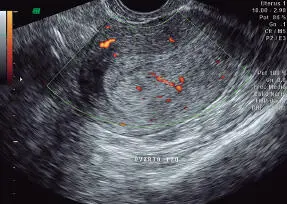

Pólipo endometrial. Puede presentarse como único o múltiples, pediculado o sésil, y su tamaño es variable. En el examen ultrasonográfico de rutina, en general se visualiza como una imagen ecogénica homogénea o zona de mayor densidad en el espesor del endometrio, o área focal de engrosamiento endometrial, siendo posible distinguir a veces con Doppler color la presencia de un vaso único nutricio. Puede visualizarse asimismo como una imagen ecogénica, con áreas econegativas en su espesor. En presencia de una colección líquida intracavitaria o endometrio trilaminar (en fase folicular, endometrio tipo I o II inicial), es posible verlo como una formación sólida focal, en que se distinguen las paredes de la cavidad de manera nítida y bien delimitadas; ejemplos complementarios: histerosonografía y ecografía 3D ( Figuras 16-13a 16-17, 16-27, 16-28y 16-54).

Figura 16-54.Vascularización de pólipo